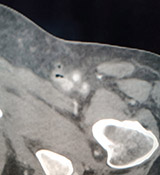

| Miositis necrotizante y flebitis enfisematosa. Se solicita exploración de MMII por descompensación grave de paciente en UCI, cuadro séptico y piel oscurecida . En la exploración ecográfica se visualiza aire en el cayado de la safena y en la pierna (sin poder establecer el plano exacto).La exploración con TAC muestra burbujas de aire en tejidos profundos, musculares, en zona tibial tanto anterior como posterior. | ||||||

| Miositis necrotizante sobre Gangrena de Fournier | ||||||

Imágenes de pacientes con Gangrena de Fournier |